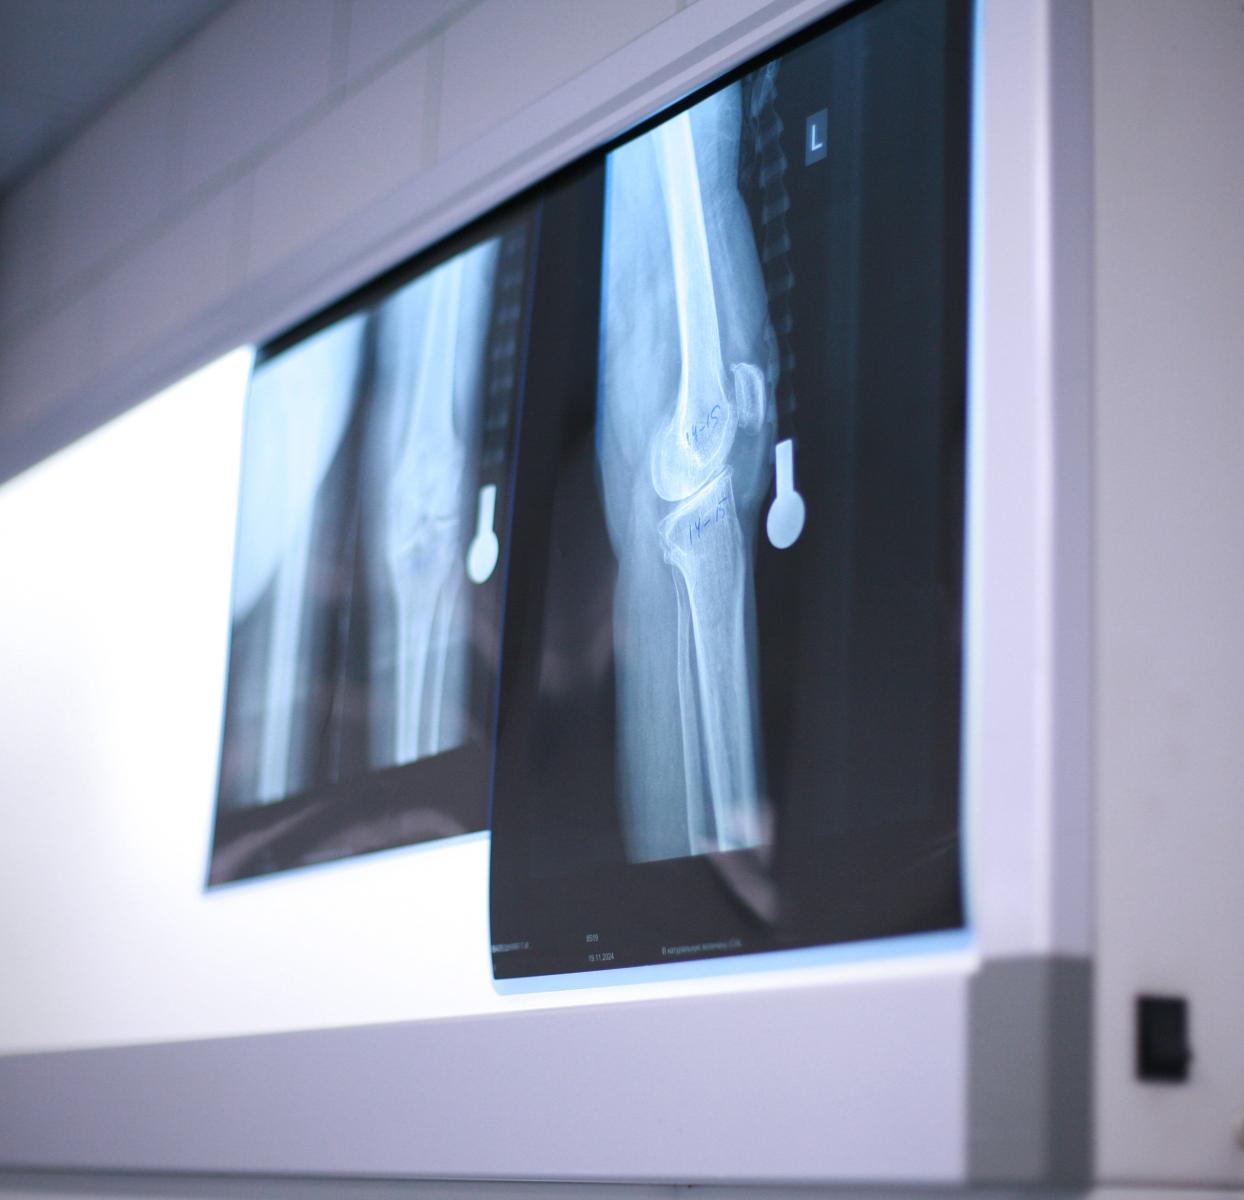

Артроскопия коленного и плечевого сустава

Специалисты отделения травматологии выполняют современные малотравматичные артроскопические операции с применением новейших технологий и имплантатов.

Артроскопия — это современный метод лечения суставов, при котором операция проводится через небольшие проколы, без больших разрезов. Это значит: минимум травматизации, максимум точности и быстрое восстановление.